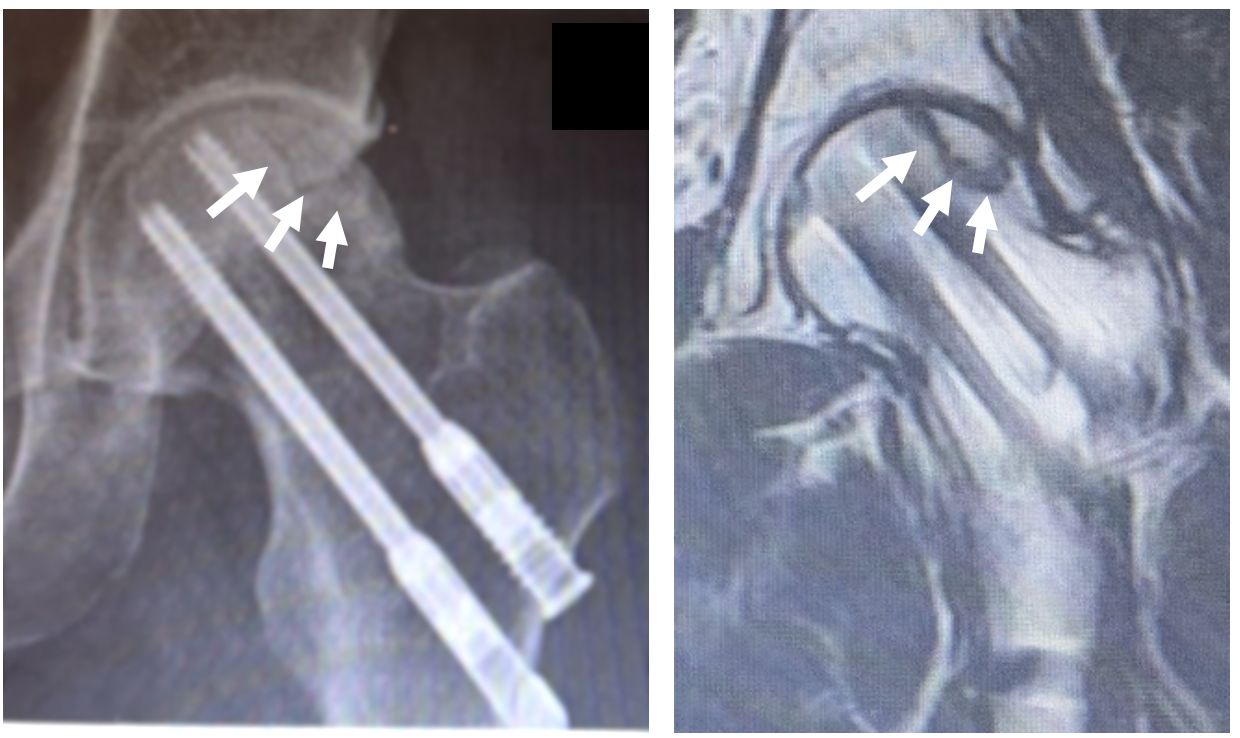

X線画像では骨折の治療の2本のスクリューがあり、その外側の体重がかかる部分にヒビが入ってきていて、MRIでも骨頭壊死と診断

マラソンで転倒され、大腿骨頚部骨折を受傷

近医で骨折手術(スクリュー2本)を施行

骨折手術後5年で左股関節の痛みを生じ、X線、

MRIで骨頭壊死を指摘された。

MRI検査

左Type C1

左Stage 3A

術前:壊死部のヒビが目立っていた

術後1年:ヒビが徐々に不明瞭  CTでも壊死部の骨再生を確認